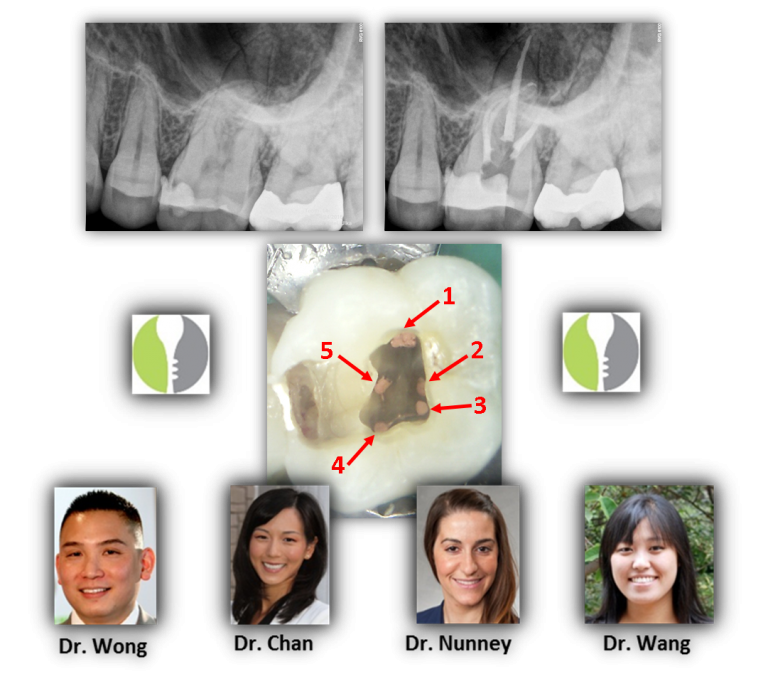

From renovoendo.com

Dental Anatomy Assisted Magnification Renovo Endodontic Studio Dental Anatomy Ct The tooth sits in alveolar processes of the upper or lower jaw and is mainly composed of dentin. Gaining knowledge of which imaging protocol to use, the relevant anatomy of the teeth and related structures, and the key imaging findings of dental emergencies will help radiologists identify infections, trauma, and complications of dental procedures. Dental anatomy and pathology encountered on. Dental Anatomy Ct.